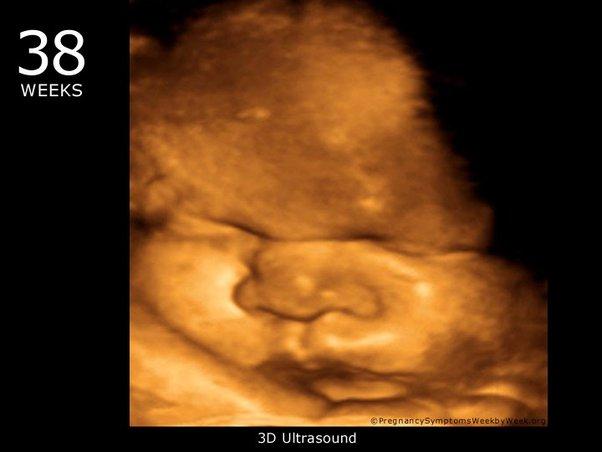

Thai nhi 38 tuần phát triển như thế nào?

Thai nhi 38 tuần nặng bao nhiêu?

Ờ tuần thai thứ 38, kích thước của thai nhi có thể so sánh tương đương với một bó xà lách lô lô.

- Cân nặng: 2,723 – 3,652 kg.

- Chiều dài: tính từ đầu đến gót chân dài khoảng 49,8 cm

Ngoài ra, dấu hiệu thai 38 tuần khỏe mạnh còn gồm các chỉ số sau:

- Đường kính lưỡng đỉnh (BPD): 84 – 99mm

- Chu vi vòng đầu (HC): 307 – 354mm

- Chiều dài xương đùi (FL): 66 – 78mm

- Chu vi vòng bụng (AC): 299 – 378 mm

Nhịp tim thai nhi 38 tuần tuổi là bao nhiêu?

- Nhịp tim thai nhi 38 tuần khoảng 110 – 160 lần/phút. Nhịp tim thai nhi có thể thay đổi từ 5 – 25 nhịp mỗi phút.

Sự phát triển của thai nhi 38 tuần tuổi

- Nhịp tim thai nhi: khoảng 110 – 160 lần/phút.

- Phổi bé đã khỏe hơn, sẵn sàng cất tiếng khóc ngay khi chào đời.

- Ruột của bé chứa đầy phân su, do tuần thai thứ 38 đã có thể nuốt nước ối.

- Làn da của bé: Bên ngoài da của bé đã mọc một lớp lông tơ, giúp giữ ấm cơ thể khi chào đời.

- Móng tay, móng chân của bé đã mọc hoàn chỉnh, phủ đủ cả ngón tay và ngón chân của bé.